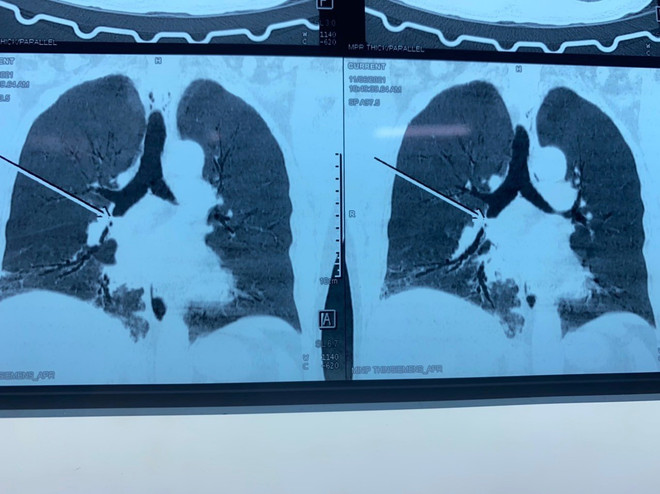

Gắp mảnh xương nằm hơn một tháng trong phế quản của bệnh nhân ảnh 1Hình ảnh chụp X quang nơi mảnh xương còn nằm trong phế quản của bệnh nhân. (Ảnh: TTXVN phát)

Sau khi khai thác bệnh sử, ghi nhận các triệu chứng của bệnh nhân, các bác sỹ Khoa Nội hô hấp-Miễn dịch dị ứng thực hiện các kỹ thuật cận lâm sàng và chẩn đoán bệnh nhân bị viêm thùy dưới phổi phải, dị vật ở phế quản trung gian phải, kèm bệnh đái tháo đường tuýp 2. Các bác sỹ đã tiến hành nội soi phế quản bằng ống soi mềm gây tê gắp dị vật.

Sau hơn một giờ, các bác sỹ gắp được dị vật là một mảnh xương lợn dài 1,5cm nằm trong lòng phế quản phải của bệnh nhân. Hiện sức khỏe bệnh nhân đã ổn định và chuẩn bị ra viện.